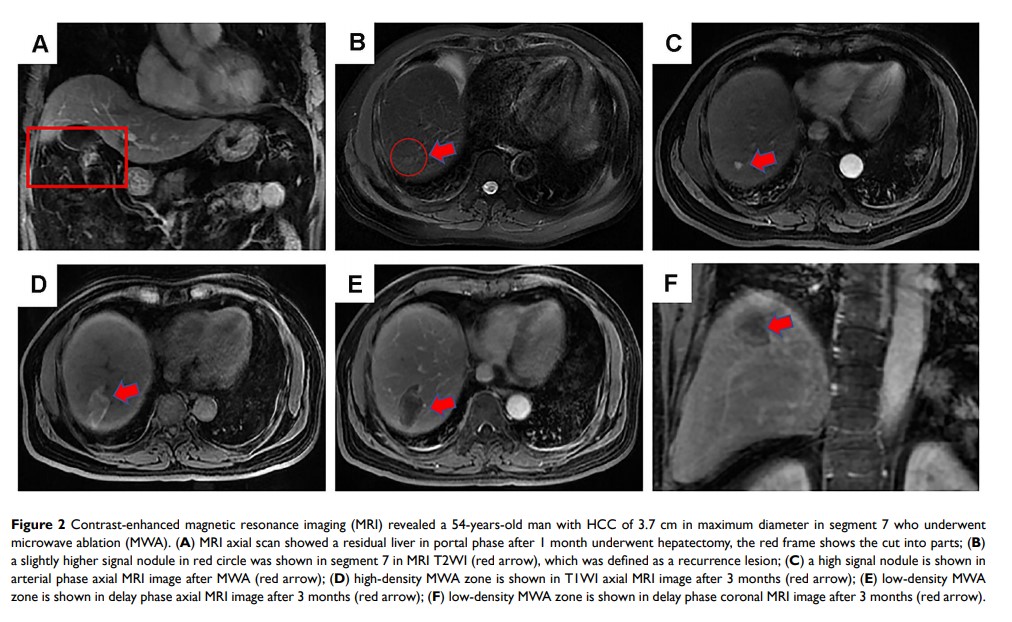

开发和验证基于临床病理学的诺模图,以预测接受肝切除术联合微波消融治疗后复发性肝细胞癌患者的生存结果